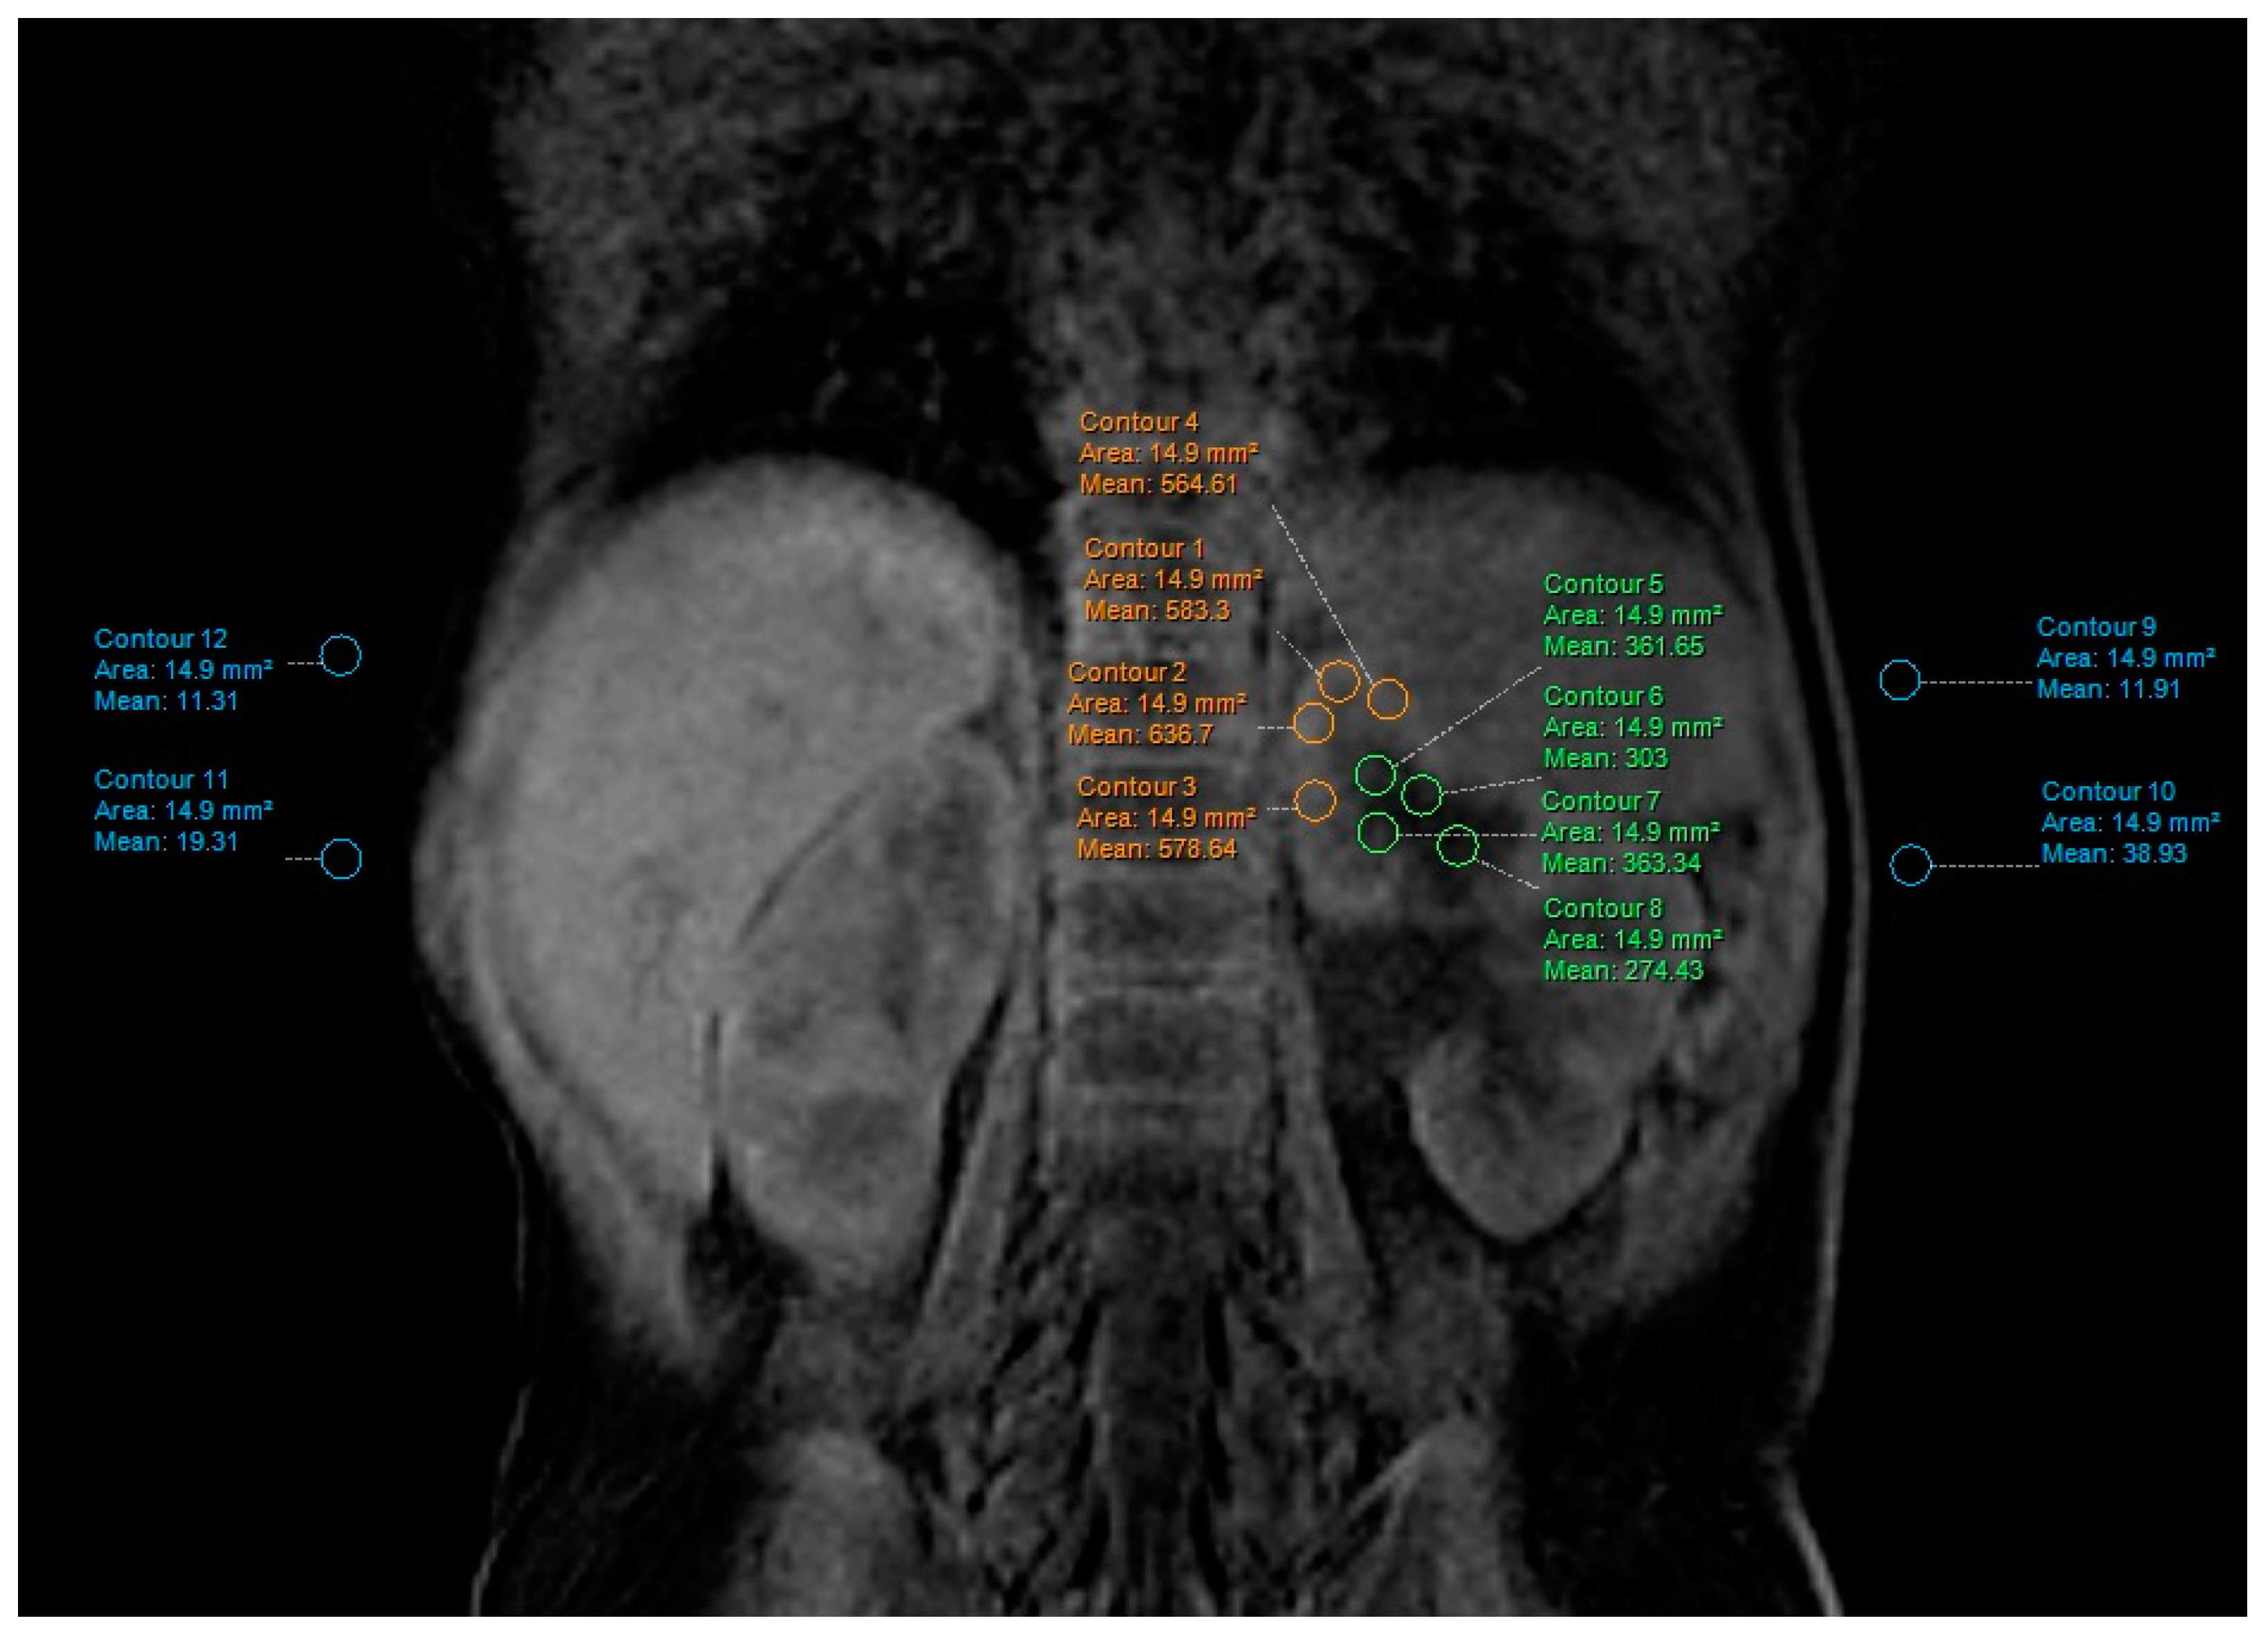

2.4. Contrast-to-Noise Ratio (CNR) and Signal-to-Noise-Ratio (SNR) Measurements